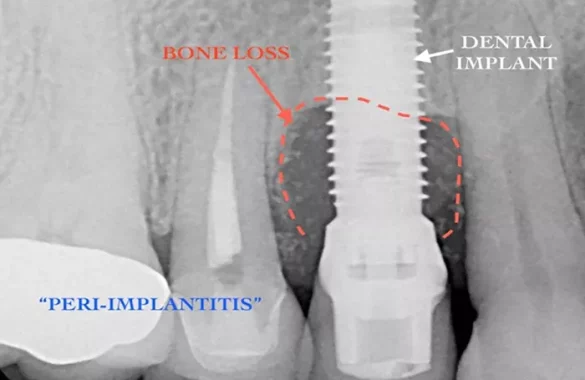

The practice reports that its methodology includes structured charting of periodontal measurements, such as probing depths and attachment levels, as well as radiographic analysis to assess bone support and anatomical features. Additional diagnostics and standard indices are used to track the status and progression of gum or implant disease. According to Pennsylvania Perio & Implants, this emphasis on quantifiable data is critical for ensuring consistent patient evaluations.

The organization also detailed its approach to evaluating potential dental implant candidates. Diagnostic imaging, anatomical review, and bone density analysis guide a systematic process rooted in research. The practice stressed that implant evaluations follow evidence-based principles and occur exclusively during clinical consultations.

Conditions such as tissue inflammation, periodontal pocketing, and bone loss require detailed assessment to understand progression, classify disease stages, and outline potential treatment options. Pennsylvania Perio & Implants emphasized that its goal is clarity in evaluation while avoiding speculation or predictive statements beyond accepted clinical standards.